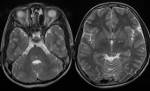

Български лекари откриха ново мозъчно заболяване

04 април 2016 09:49

Eкспертен екип от УМБАЛ Александровска в София откри рядко генетично заболяване, близко до болестта на Алцхаймер.

Проф. Лъчезар Трайков... » повече